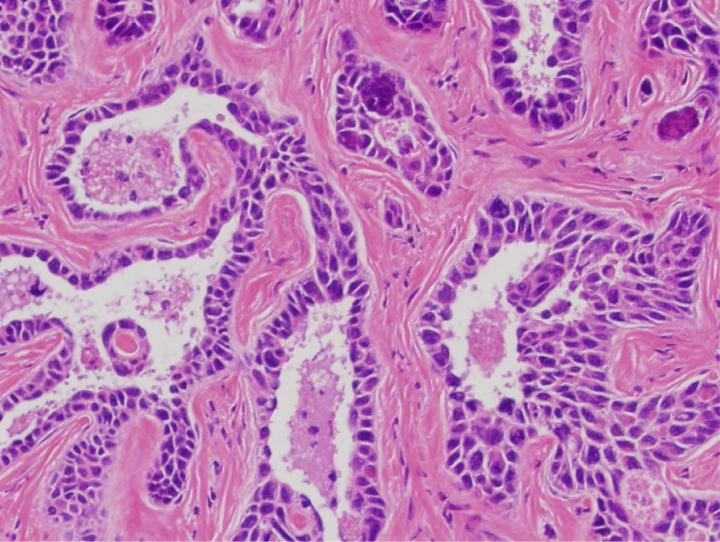

image: Histology of a liver cancer that is deficient for ARID1A and ARID1B.

ARID1A is closely related to another protein known as ARID1B, which is also unique to cBAF. It has been shown that some cancer cells need at least one ARID1 protein to survive. To examine whether simultaneous loss of both ARID1A and ARID1B would be more likely to cause or kill cancer cells, researchers eliminated or knocked out both genes in mice. Strikingly, the loss of both ARID1A and ARID1B genes resulted in aggressive liver and skin cancer formation within weeks.